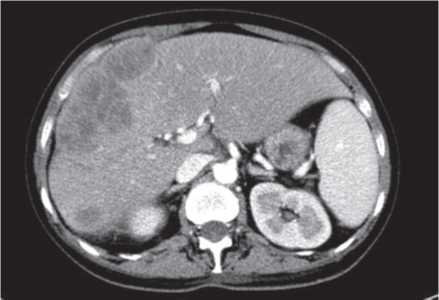

Через 6 мес от начала терапии при контрольном обследовании на КТ с контрастированием было зарегистрировано уменьшение суммы таргетных очагов до 184 мм (-9% от исходной), что соответствует стабилизации по критериям mRECIST (рис. 5, 6).

Рис. 6. КТ ОБП через 6 мес от начала терапии ленватинибом, венозная фаза. Сумма наибольших диаметров таргетных очагов 184 мм.

Fig. 6. Venous phase abdominal CT scans 6 months after starting lenvatinib therapy. The sum of the longest diameter of the target lesions is 184 mm.

При последующем исследовании в феврале 2017 г. выявлено уменьшение суммы диаметров до 157 мм (-23% от исходной), а в августе 2017 г. зафиксирован небольшой рост таргетных очагов на 3%, что расценено как стабилизация заболевания (табл. 1).